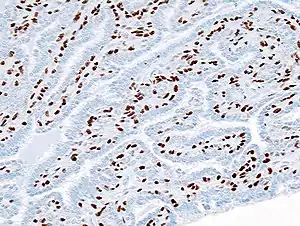

| Histopathology of intraductal papilloma of the breast by excisional biopsy. Immunostaining for p63 protein. | |

_p63.JPG.webp)